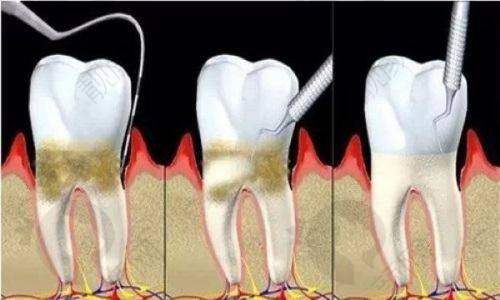

佛山春芽口腔医院在种植牙领域紧跟国内外口腔医学发展潮流,引进了多种新型的种植技术和设备。比如即刻种植技术,以往传统种植牙可能需要较长的等待时间,而即刻种植可以在拔牙后马上进行种植,大大缩短了患者缺牙的时间,减少了多次手术的痛苦。还有微创种植技术,通过微小的切口进行种植操作,术后修复更快,疼痛和肿胀也明显减轻。